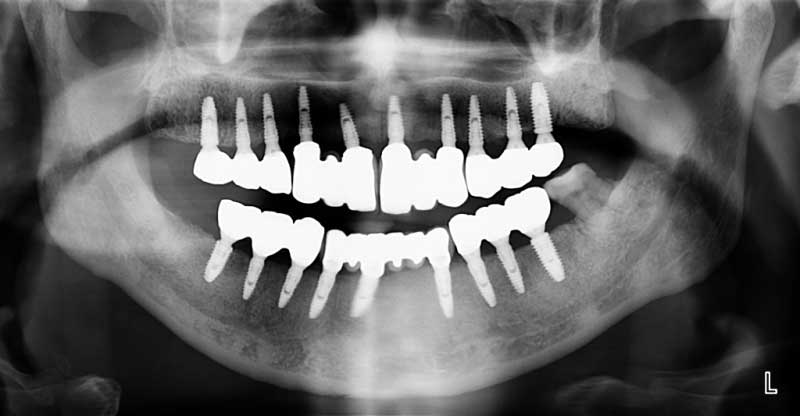

案例2